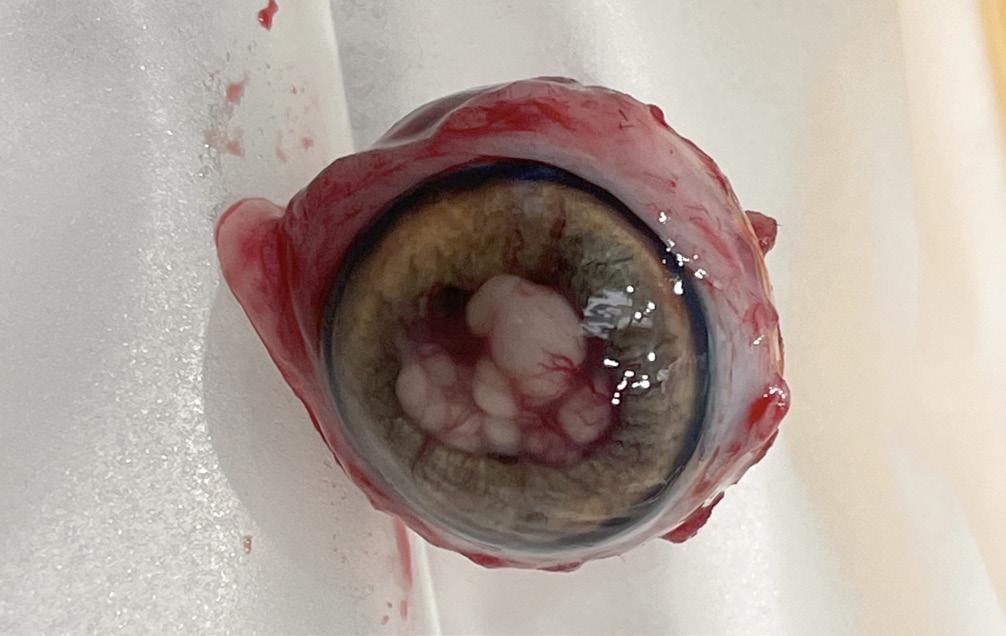

Gross Specimen Photography

Uveal Melanoma with Extra Ocular Extension

Belinda Rodriquez

Murray Ocular Oncology and Retina

Miami, Florida